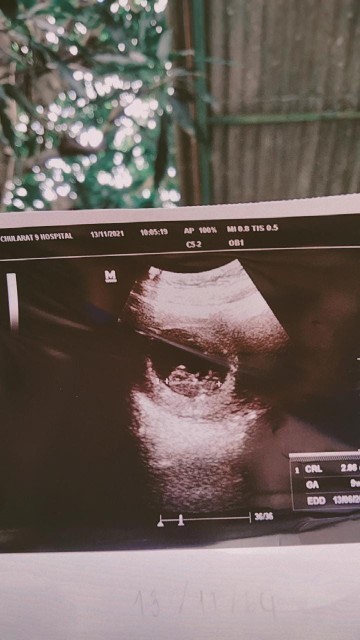

ประมาณ 3 เซนค่ะ 10 วีค

เข้า10 w เเล้วค่ะ👼❤️